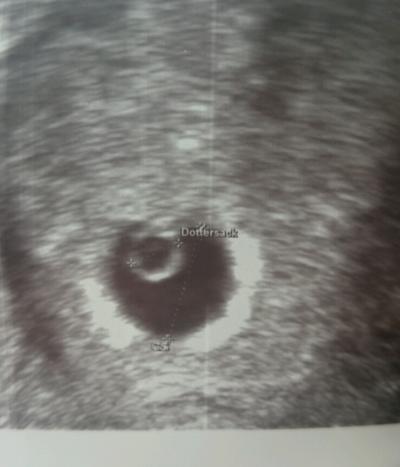

Man sah Fruchthöhle und Dottersack. Er meinte alles zeitgerecht entwickelt. Jetzt muss ich nächste Woche Mittwoch nochmal hin, also heißt es weiter warten und Angst haben deswegen wollte ich nicht so früh ein Termin, weil ich mir jetzt als sorgen mache, ob nächste Woche wirklich da ein Herzschlag ist

Bei mir war es gestern genauso. Bin heute 6+4 und gestern hat der Frauenarzt eine Fruchthülle und das Embryo gesehen. Er meinte auch dass seit der letzten Untersuchung alles schön gewachsen ist. Aber man konnte den Herzschlag nicht sehen. Wie weit bist du genau? Ich drücke dir ganz fest die Daumen.

Heute 6+0 Dann bin ich erleichtert, dass man bei dir auch nicht mehr gesehen hat.

Huhu du.... Mein Frauenarzt hat mir auch gesagt, dass man in der 6. Woche die Fruchthöhle mit Dottersack sieht und mehr meist noch nicht, es kommt auf die Lage an und das Ultraschallgerät. Man konnte bei mir z.B. auch nur ein Flimmern erkennen wo der Arzt gesagt hat, da wird schon weiss sein, nur der Doppler z.B. konnte es auch noch nicht erfassen. Er sagte das ist noch zu früh, ist einfach ganz normal. Er sagte mir wenn ich dann so 10 Tage später da bin, dann wird man es hoffentlich richtig sehen und messen können. Also keine Sorge bei dir ist auch alles ganz normal und es wird sicher alles gut gehen :-*